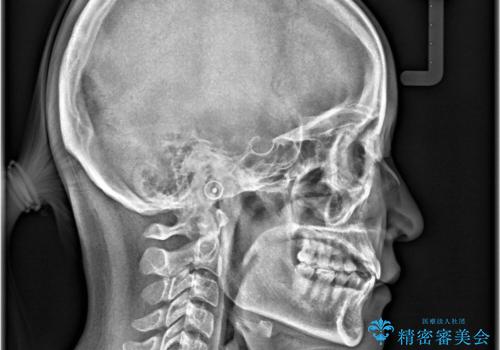

下顎前歯に叢生があり、右上2は反対咬合の状態でした。

昔から食いしばりがあるのを患者様が自覚されており、そのせいか口が開けにくいことも悩まれていました。

下顎前歯の叢生がとれ右上2の反対咬合も改善し患者様にも満足していただけました。治療期間は1年~1年半を見込んでいましたが、患者様の協力もあり10か月で矯正を終えることが出来ました。